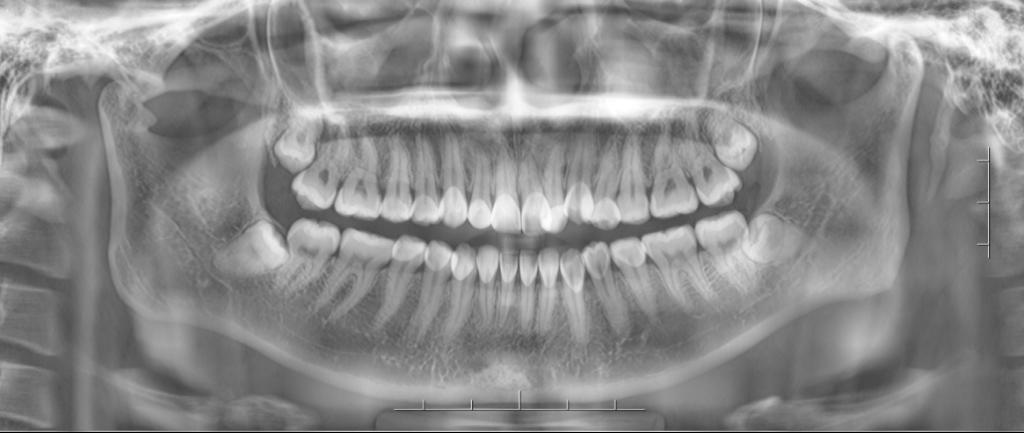

1、阻生齿长轴与第二磨牙长轴关系分类:垂直阻生、近中阻生、水平阻生、倒置阻生、远中阻生、舌向阻生和颊向阻生。

2、阻生齿相对于第二磨牙拾平面的位置关系分:高位阻生、中位阳生和低位阻生。

3、阻生齿和下颌支前缘相对位置关系分为以下三类:

Ⅰ类:阻生牙牙冠的近远中径完全位于下颌支前缘的前方。

Ⅱ类:一半以内的阻生牙牙冠的近远中径位于下颌支内。

Ⅲ类:一半以上的阻生牙牙冠的近远中径位于下颌支内。